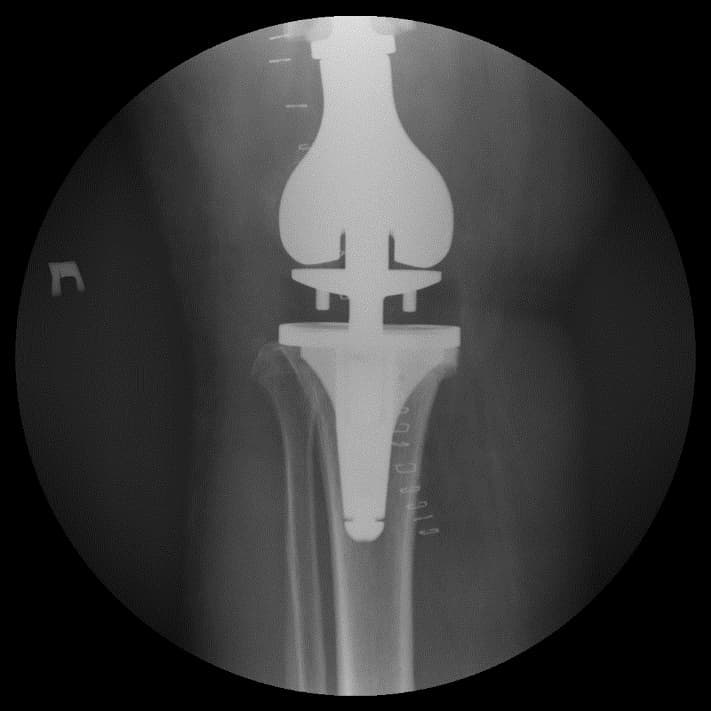

Үе дайрсан ясны анхдагч хавдар, ясны дутмагшлын үед хийгдэх мэс засалimg22Үе дайрсан ясны анхдагч хавдар, ясны дутмагшлын үед хийгдэх мэс засалimg23

Зураг 1. Сэргээн засах мэс заслын өмнөх рентген зураг. Эгц урд, хажуугаас авсан байдал.

Үе дайрсан ясны анхдагч хавдар, ясны дутмагшлын үед хийгдэх мэс засалimg24Үе дайрсан ясны анхдагч хавдар, ясны дутмагшлын үед хийгдэх мэс засалimg25

Зураг 2. Мэс заслын дараах рентген зураг. Эгц урд, хажуугаас авсан байдал

Өвдөгний үений шөрмөсөн холбоосууд үрэвслийн улмаас бүрэн гэмтсэн Дунд чөмөг - шилбэ ясны дутмагшилтай учир дунд чөмөг-өвдөгний хавдрын протез сонгон суулгасан. Энэ дунд чөмөг-өвдөгний хавдрын протез нь мөн hinge system- тэй.